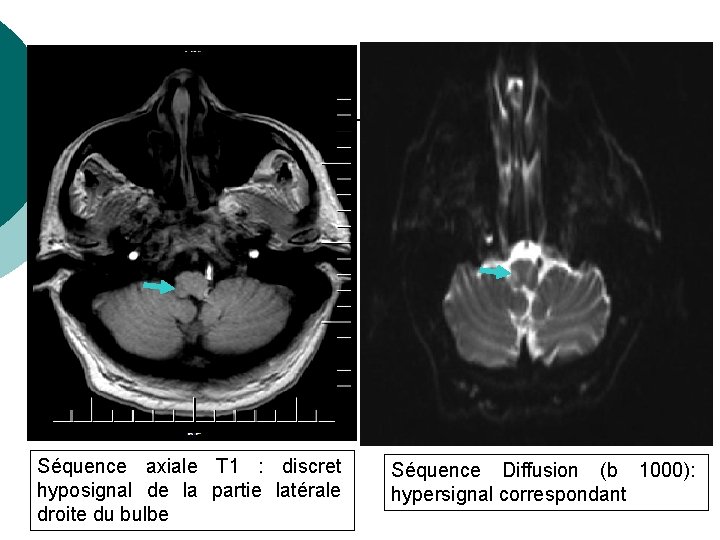

RESULTATS Séquence axiale T 1 : discret hyposignal de la partie latérale droite du bulbe Séquence Diffusion (b 1000): hypersignal correspondant